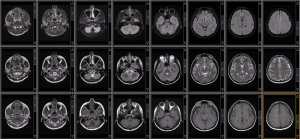

Probing White Matter Microstructure With Diffusion-Weighted MRI: Techniques and Applications in ADRD

Shruti Mishra, MD